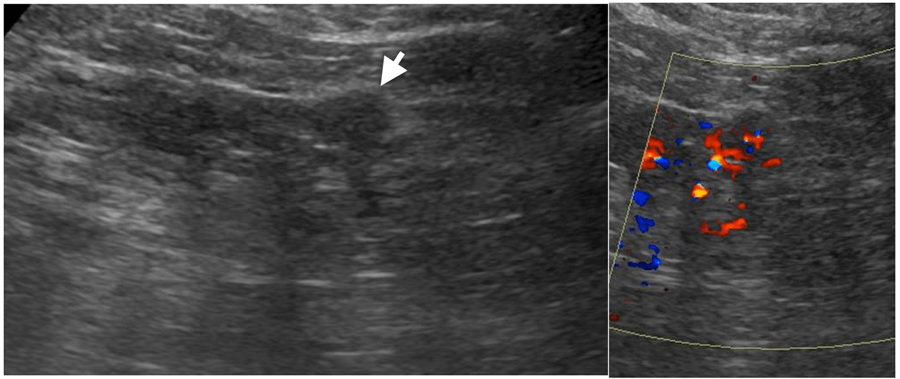

On ultrasound, solid renal masses are conspicuous only when their echogenicity is different from the adjacent renal parenchyma, there is distortion of normal renal contour or there is abnormal vascularity on colour doppler (Figure 2).

Figure 2: Small partly exophytic RCC on ultrasound (left).

Internal vascularity demonstrated on colour Doppler (right).